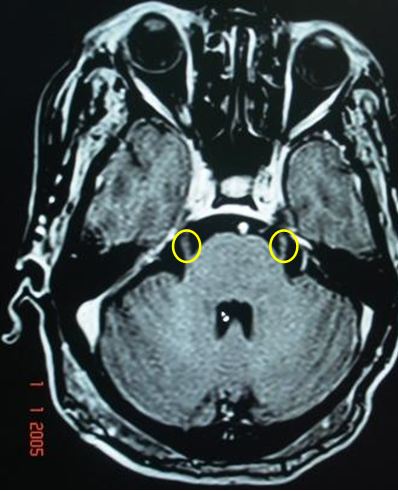

Trên hình ảnh MRI sọ não cắt qua cầu não, xung T1, hình ảnh dây thần kinh số 5( Dây thần kinh sinh ba) hai bên rất rõ

Kế hoạch xạ phẫu Gamma: Đặt 1 shot 4mm vào rễ dây thần kinh số 5 bên phải tại vị dây thần kinh đi vào cầu não. Đường tròn màu vàng là đường đồng liều 50% tương ứng 30 Gy.